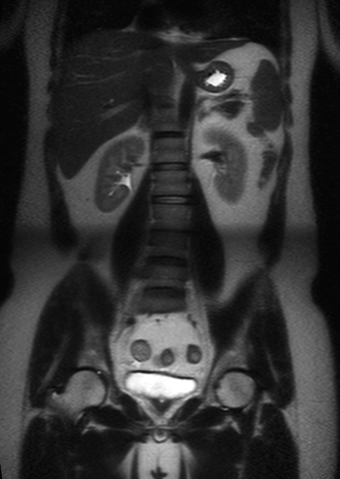

RM Pelvis

Prueba diagnóstica no invasiva que consiste en la obtención de imágenes de alta definición anatómica de la pelvis mediante el empleo de un campo electromagnético y ondas de radio (con un emisor y un receptor). No utiliza radiación ionizante. Se realiza para estudiar patologías del útero, del ovario, de las trompas y la vagina, ya sean de origen tumoral, inflamatorio o vascular. Esta prueba permite valorar órganos como la vejiga urinaria, la unión entre los uréteres y la vejiga, la próstata, las vesículas seminales, la uretra, los huesos de la pelvis, etc A veces requiere el uso de contraste intravenoso (Gadolinio) para caracterizar las lesiones.